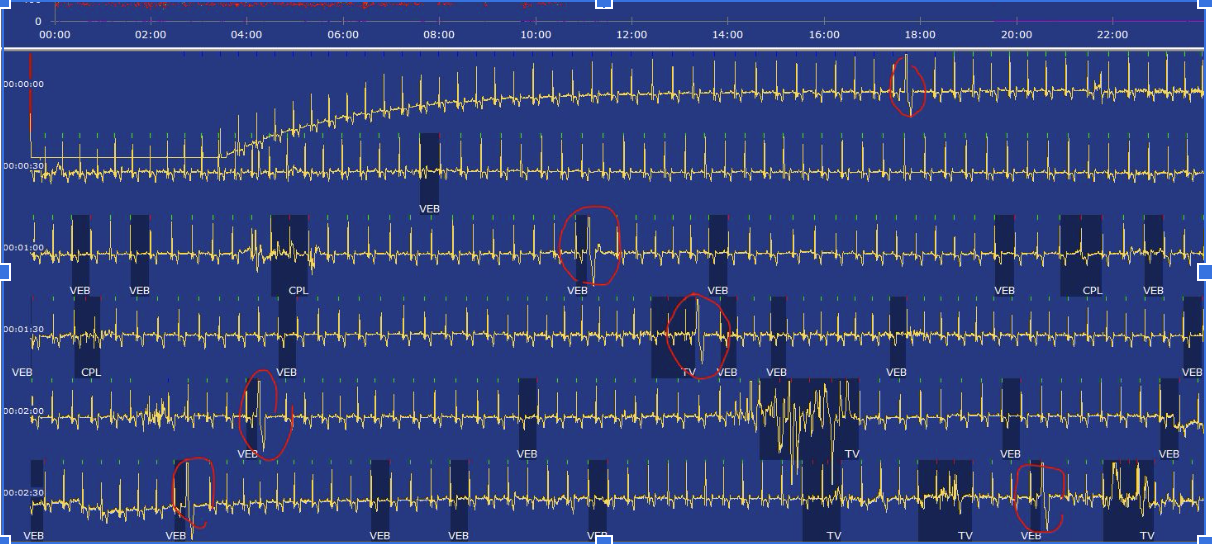

L’enregistrement Holter est un examen non invasif qui permet d’enregistrer le tracé ECG d’un animal sur une période longue (24-48 heures en règle générale).

En comparaison à l’électrocardiogramme, enregistré couramment sur une à plusieurs minutes en consultation, l’examen Holter permet d’enregistrer un tracé incluant les activités normales de l’animal au cours de la journée (sommeil, promenade, jeux…).

Cet outil diagnostique est donc plus complet que l’ECG et permet de mettre en évidence des troubles du rythme importants que l’électrocardiogramme pourrait manquer.